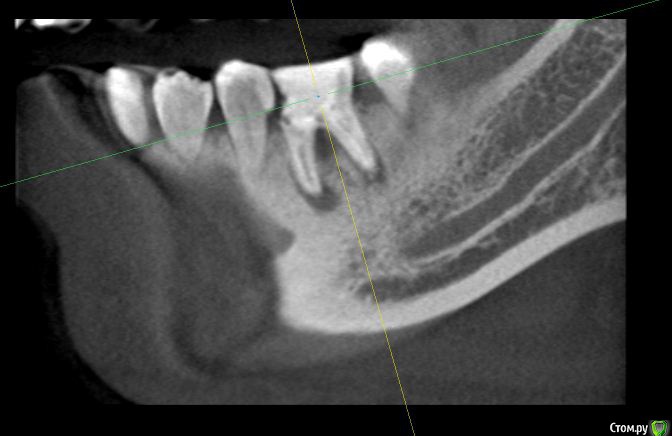

alex_ts Опубликовано 7 ноября, 2016 Поделиться Опубликовано 7 ноября, 2016 (изменено) Здравствуйте. Периодически беспокоит нижняя 6ка, 3 года назад она была на 3/4 разрушена и там стояла "металлическая" черная пломба, от которой зуб приобрел синий оттенок. На мой вопрос что его наверное надо удалять, стоматолог на меня тогда удивленно посмотрела и сказала что корни хорошие и ничего удалять не надо. Тогда же она поставила очень большую пломбу, сказав что это не на долго и так или иначе придется одевать коронку. Сейчас зуб время от времени побаливает и иногда кровит. Сходил в клинику, сделали кт зуба. Врач сказала что варианта 2, либо долго и сложно лечить этот зуб и протезировать, но без гарантии, так как там затемнение в области фуркации, либо удалять и ставить имплант. Что вы порекомендуете в данной ситуации? Спасать зуб или лучше будет избавиться от него? Мч, 24 года Изменено 7 ноября, 2016 пользователем alex_ts Ссылка на комментарий

IvanK Опубликовано 9 ноября, 2016 Поделиться Опубликовано 9 ноября, 2016 +1, удалять убрать нависающий край пломбы на 5ке Ссылка на комментарий

alex_ts Опубликовано 15 ноября, 2016 Автор Поделиться Опубликовано 15 ноября, 2016 Спасибо всем за ответы, действительно придется удалять.Чтобы не создавать отдельной темы, хочу еще спросить, можно ли установить имплант одномоментно с удалением в моем случае, при том что зуб слегка ноет время от времени и есть боль при надавливании на десну в области корня+ иногда кровоточит десна. Просто хирург предложил сделать сразу, но врач которая делала снимок сказала что нужно подождать. Ссылка на комментарий